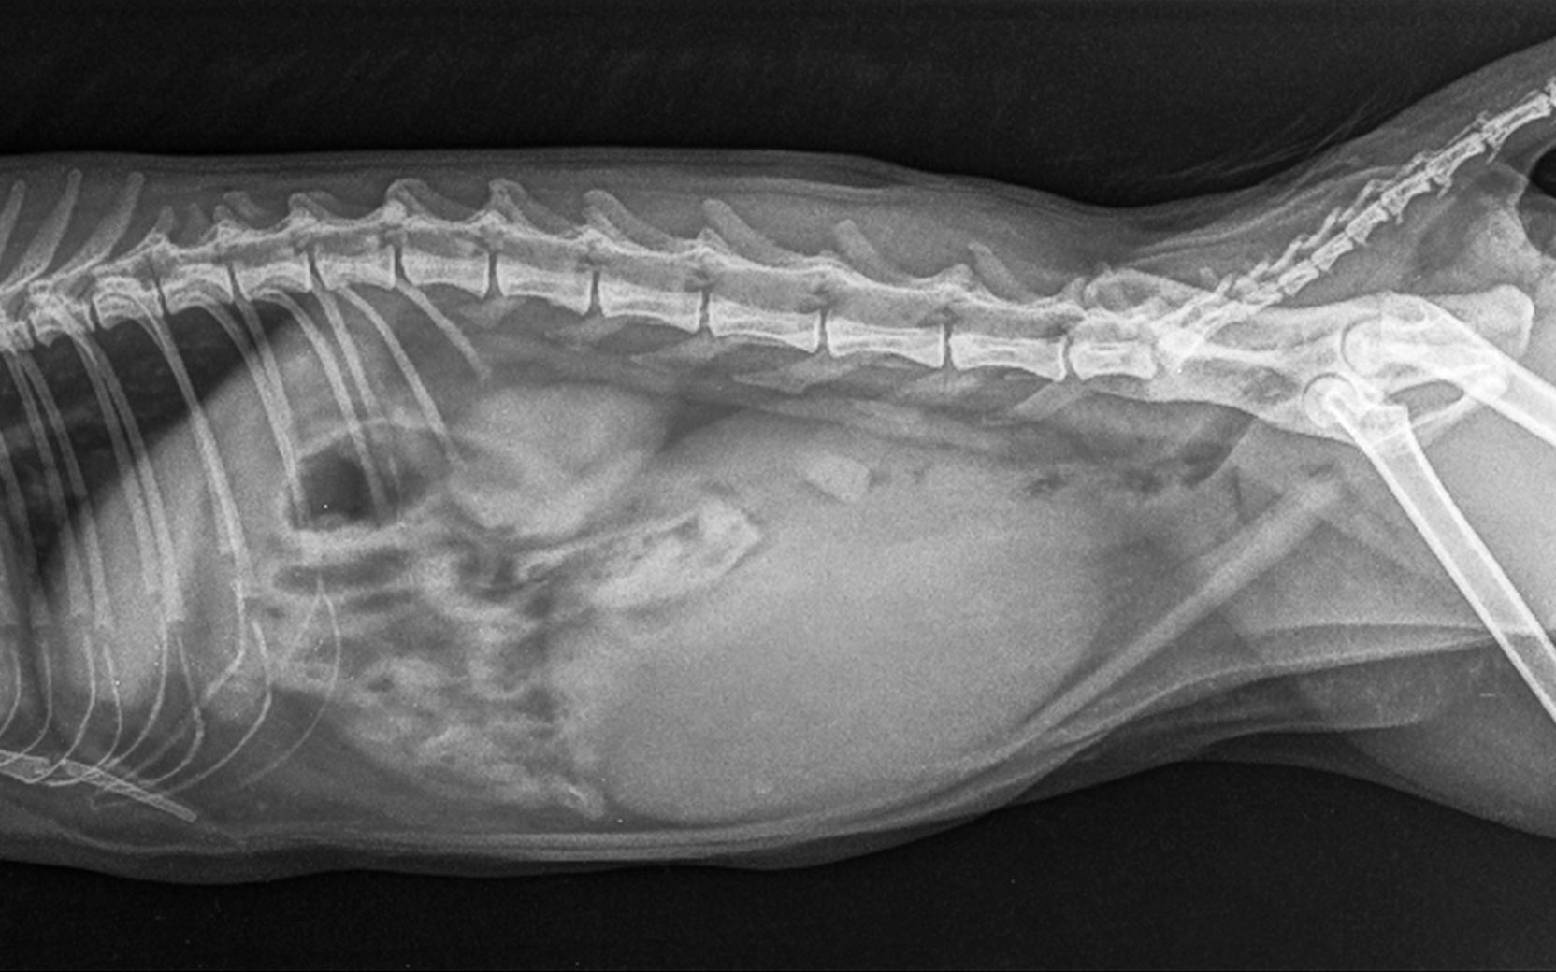

X-ray examinations enable the visualization of tissues inside the body. The higher the density of individual tissues, the more radiation is absorbed and the less is transmitted. Tissues that absorb a lot of X-rays, such as bone tissue, appear bright on the X-ray image. A lot of radiation passes through soft tissues and cavities onto the X-ray film. These areas appear dark or even black on the image.

Since the X-ray image is only a two-dimensional representation of what is actually a three-dimensional object, several images are usually taken at different angles in order to reliably detect changes such as bone fractures.